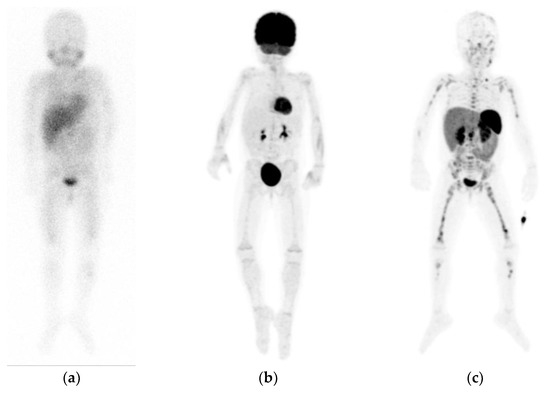

- Pauwels, E.; Celen, S.; Vandamme, M.; Leysen, W.; Baete, K.; Bechter, O.; Bex, M.; Serdons, K.; van Laere, K.; Bormans, G.; et al. Improved resolution and sensitivity of [18F]MFBG PET compared with [123I]MIBG SPECT in a patient with a norepinephrine transporter–expressing tumour. Eur. J. Nucl. Med. Mol. Imaging 2020. [Google Scholar] [CrossRef]